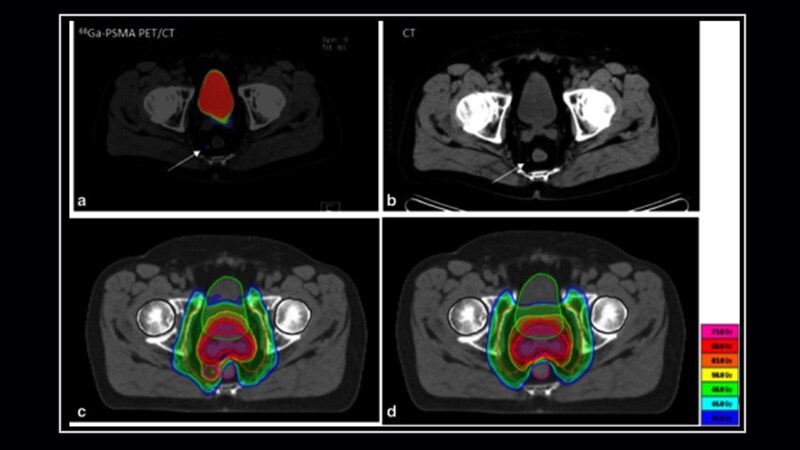

EAU 2023Digital Rectal Exam Fails as Prostate Cancer Screening ToolA large study from Germany found that digital rectal examination had low detection rates compared with prostate-specific antigen testing in men in their mid-to-late 40s.

EAU 2023'Very Good News' About Localized Prostate Cancer: ProtecT ResultsMen with newly diagnosed non-metastatic prostate cancer who were randomly assigned to surgery, radiation, or active monitoring had similar overall and prostate cancer-specific survival rates after 15 years.